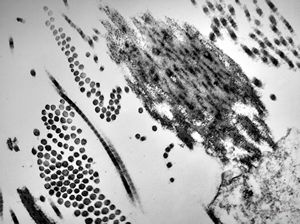

F, 24y. | molluscum contagiosum … virions

F, 24y. | molluscum contagiosum

F, 7y. | molluscum contagiosum … virions